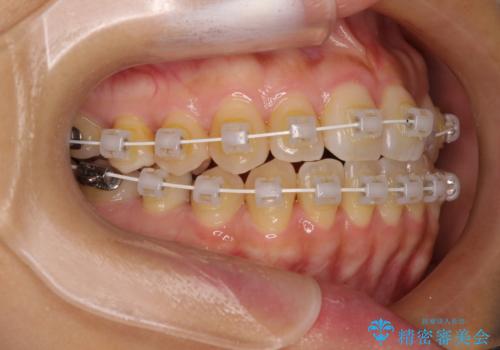

クロスバイトの前歯を改善 ワイヤー装置で楽々矯正治療

- 矯正装置

- 審美装置

- 前歯のクロスバイトを改善したいとのことで来院された患者様です。

マウスピース矯正は自己管理が煩わしいとのことで、ワイヤー装置による矯正治療を行うこととしました。

舌の突出癖が認められたため、デコボコ改善に伴い前歯が前突する可能性があったため、舌のトレーニングをしっかりと行うよう指導しながら治療を進めることとしました。